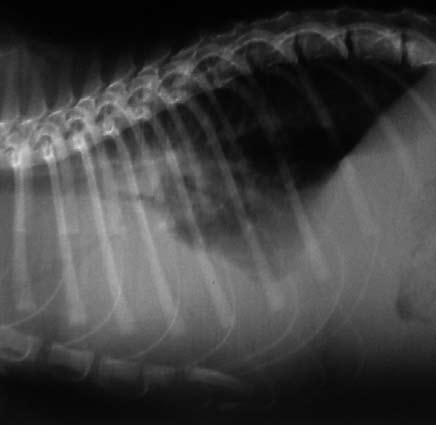

- o formă exsudativă (umedă), caracterizată prin poliserozită (ascită, exsudat toracic şi/sau pericardic) şi vasculită.